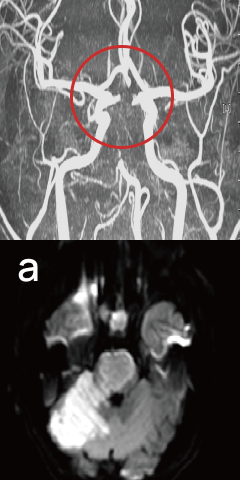

뇌졸중

Stroke-

발병시

-

줄기세포 치료 15일 후

줄기세포 치료 41일 후

끊어진 뇌혈관 주변으로 새로운 혈관이 형성 되었습니다.